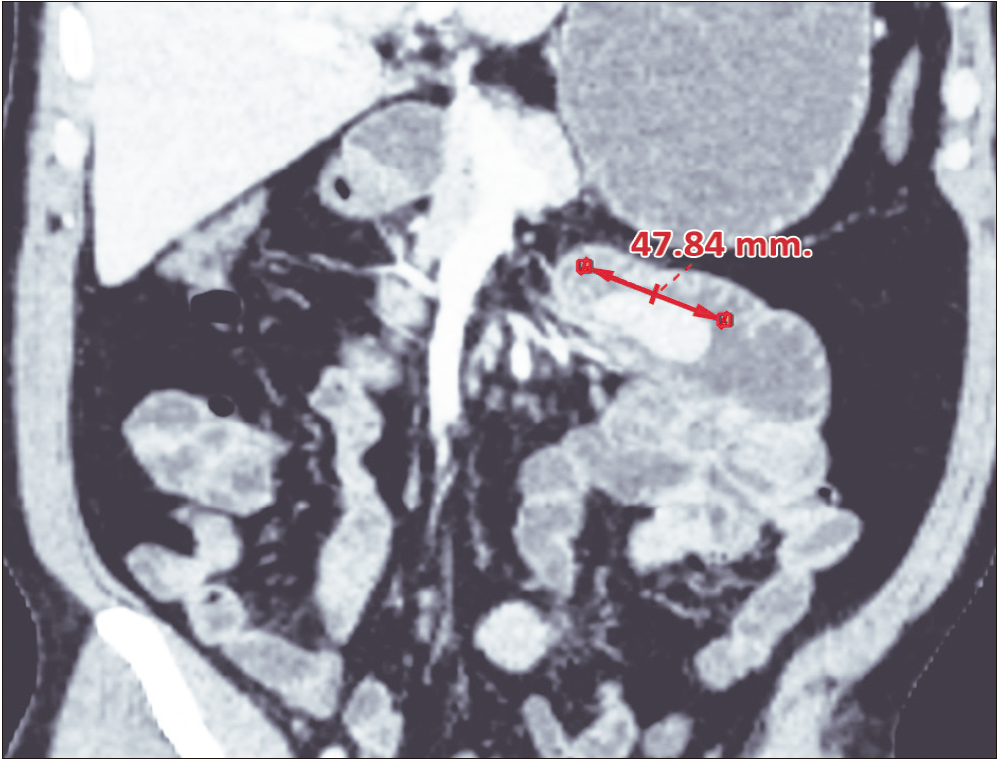

Se solicitó una enterotomografía que mostró una imagen protruida, con pedículo ancho de aspecto heterogéneo, de 47 mm aproximadamente, a nivel de la tercera y cuarta porción duodenal, con marcado realce tras la administración de contraste endovenoso. (Figura 3).

Figura 3. Enterotomografia computarizada con contraste. A nivel de la tercera y cuarta porción

duodenal una imagen polipoidea de aproximadamente 47 mm de longitud protruye en la luz intestinal